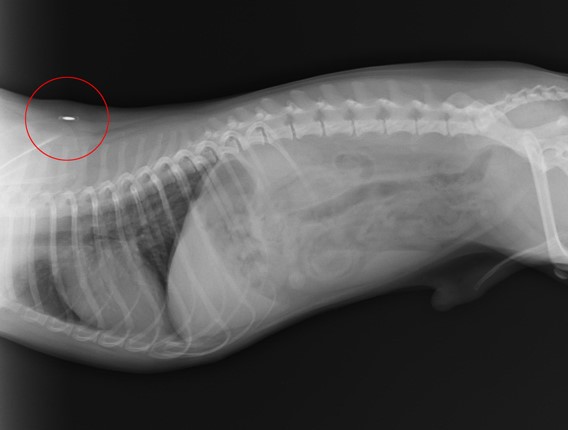

Микрочипът е миниатюрен имплант, затворен с капсула от специален биосъвместим материал, напълно безвреден за Вашия любимец. Размерът му е колкото оризово зрънце. Всеки чип съдържа уникален идентификационен номер, който не може да бъде променян.

Имплантирането става подкожно чрез специална спринцовка с игла, в която е разположен чипът. Манипулацията е напълно безболезнена за домашния любимец. Веднъж имплантиран, микрочипът остава под кожата до края на живота. За повечето страни от ЕС мястото на имплантиране е отляво на шията.

Разчитане. Номерът на микрочипа може да бъде разчетен с електронно четящо устройство. Прочитането на импланта става след доближаване на четеца в близост до животното. При микрочипирани животни на дисплея на четеца се изписва комбинацията от цифри, която се съдържа в чипа.